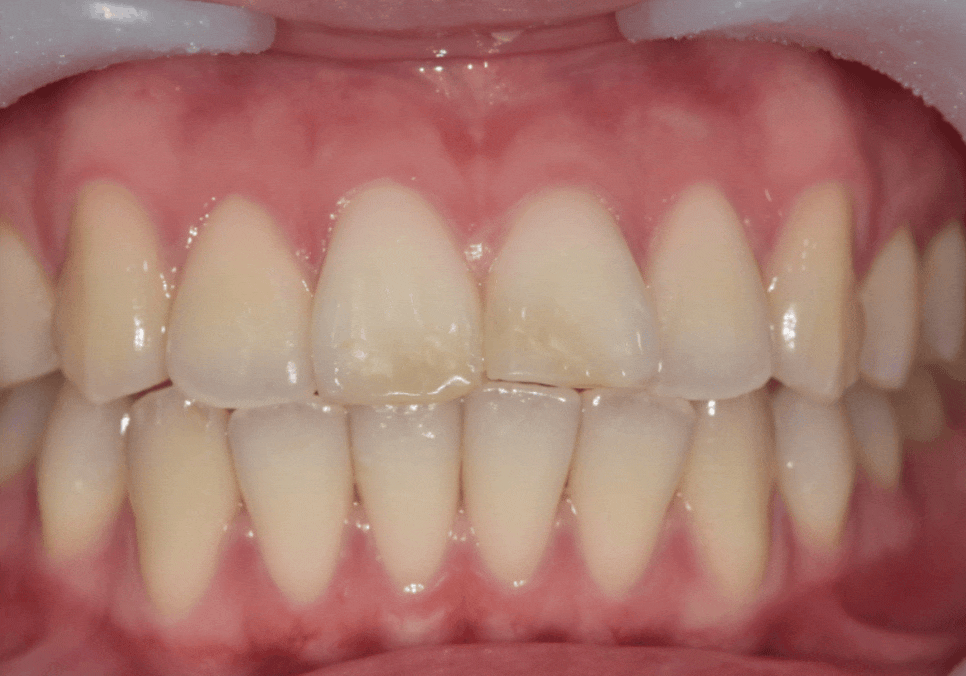

이러한 조건을 고려해

라미네이트로 기능과 심미를

동시에 잡는 방향으로 결정했습니다.

라미네이트가 오래 버티려면

앞니끼리 정면충돌하지 않도록 만드는 것이 핵심입니다.

그래서 아주 얇은 여유 공간을 만들어 주는 것이 중요했습니다.

250403

저희 병원의 강점인 원내 기공소를 통해

기공사와 바로바로 소통하며

· 앞니 돌출감을 얼마나 줄일지

· 길이를 어떻게 맞출지

· 힘이 덜 받는 각도를 어떻게 잡을지

이런 요소들을 실제 구강 상황과 비교해

즉각적으로 조정할 수 있었습니다.

250410 절단교합으로 인한 앞니 레진 깨짐, 교정 없이 해결한 사례

단순히 “예쁘게 만드는 라미네이트”가 아니라

파절 위험을 낮추는 기능적 디자인으로

완성된 것이죠.

250203(전) 250410(후)

최종 라미네이트를 부착한 모습입니다.

· 양쪽 앞니 길이가 가지런해지고

· 앞으로 뻗어 보이던 느낌도 자연스럽게 완화되고

· 절단교합에서도 힘을 덜 받도록 안정적인 공간이 확보되었습니다.